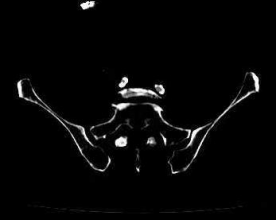

术前CTA:腹主动脉及双下肢动脉粥样硬化改变,左股浅动脉中下段重度狭窄接近闭塞,左股浅动脉下段、腘动脉、膝下分支多处钙化病变。

左侧股浅动脉中下段局部重度钙化狭窄闭塞,左股浅动脉下段,腘动脉局部中度钙化狭窄。

股浅动脉

腘动脉